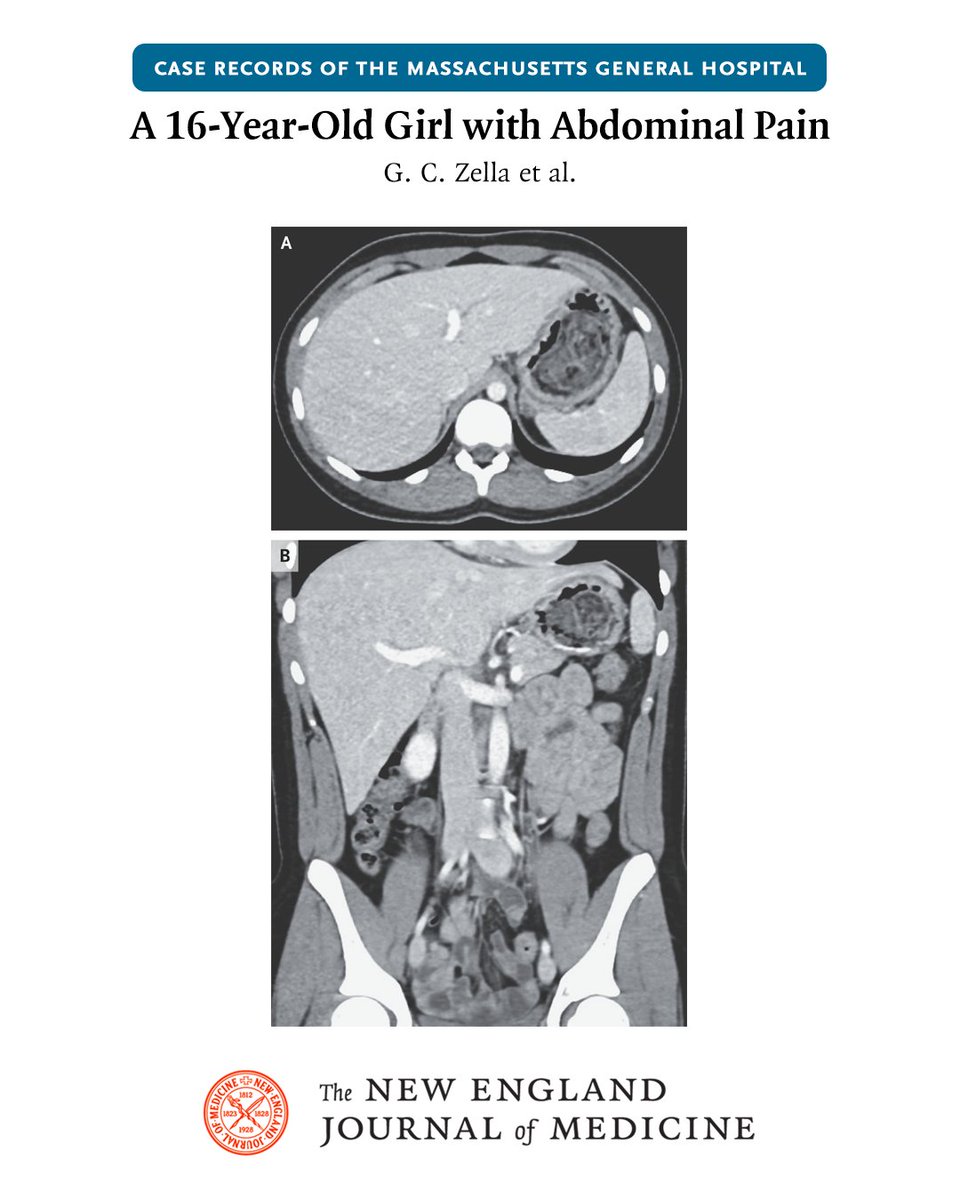

Check out our case in @NEJM @mghfc @CeliacResearch @MGH_GI

@NEJM

NEJM

1 year

A 16-year-old girl was admitted to the hospital because of abdominal pain, nausea, and vomiting. Abdominal tenderness and guarding with palpation were present. A diagnosis was made. Read the latest Case Record of the MGH (@MassGeneralNews): https://t.co/GrII7qWmPv